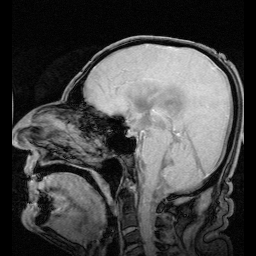

Спинномозгова́я жидкость (лат. liquor cerebrospinalis[1], цереброспина́льная жидкость, ли́квор) — жидкость, постоянно циркулирующая в желудочках головного мозга, ликворопроводящих путях, субарахноидальном (подпаутинном) пространстве головного и спинного мозга[2].

Ликвор образуется в мозге: в эпендимальных клетках сосудистого сплетения (50—70 %), вокруг кровеносных сосудов и вдоль желудочковой стенки. Далее цереброспинальная жидкость циркулирует от боковых желудочков в отверстие Монро (межжелудочковое отверстие), затем вдоль третьего желудочка, проходит через Сильвиев водопровод. Затем проходит в четвёртый желудочек, через отверстия Мажанди и Лушки выходит в субарахноидальное пространство головного и спинного мозга. Ликвор реабсорбируется в кровь венозных синусов и через грануляции паутинной оболочки.